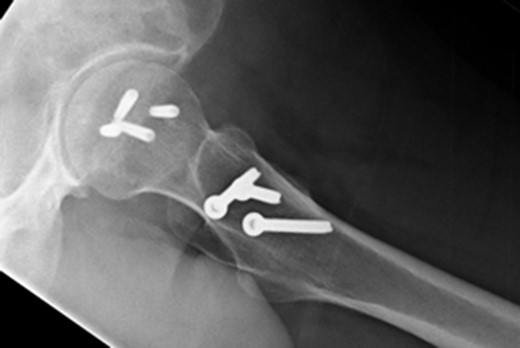

In addition to the bony injury, labral detachment and tearing were noted (later repaired with suture anchors). The femoral head was comminuted and had areas of missing articular cartilage especially posteriorly and superiorly with a 1 × 1 cm2 area of full thickness cartilage loss (Fig. 4). The weight-bearing zone was relatively unaffected. The ligamentum teres had to be released to allow fracture reduction and fixation with four headless compression screws (Fig. 5). A good fixation was achieved. Microfracture was performed on the articular cartilage defect. The femoral head, fracture fragment and microfracture site were bleeding and appeared viable.

At 14 months postoperative, the patient is pleased with his progress. There is no radiographic evidence of avascular necrosis at this stage (Figs 6 and 7). He regularly participates in activities such as cycling, and scores well on the modified Harris Hip Score (81/100), non-arthritic hip score (92.5/100) and SF-12 (41/48).